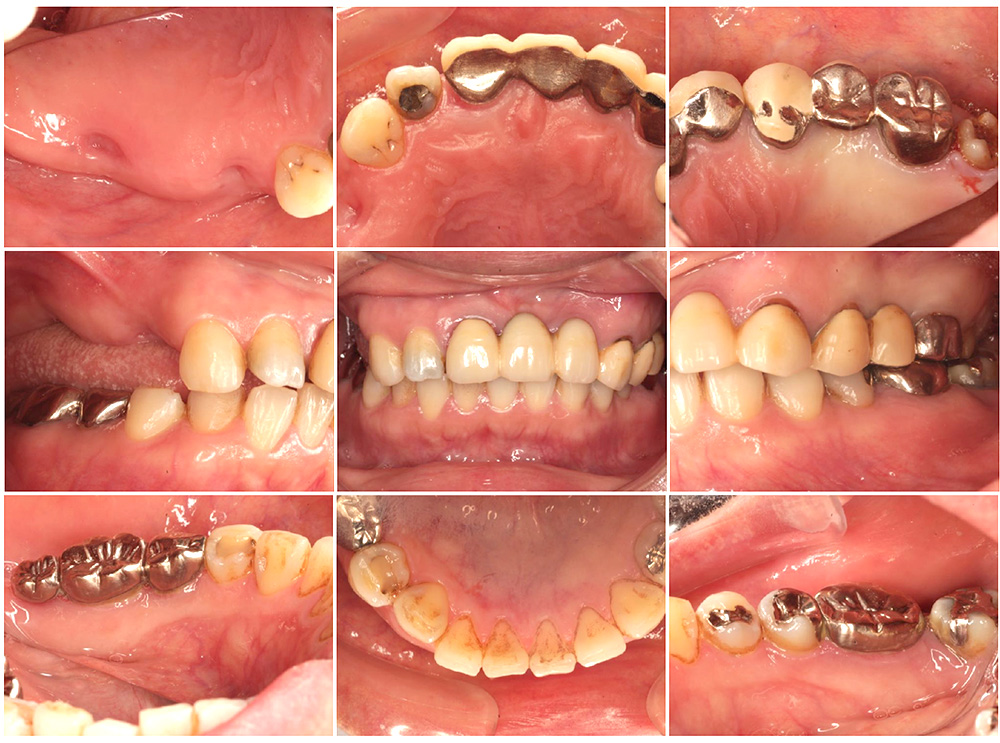

症例紹介